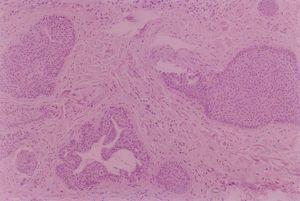

Se realizó extirpación quirúrgica de ambas lesiones (figs. 2 y 3).

Fig. 3.—Algunos de los nidos muestran diferenciación ductal. (Hematoxilina-eosina, ×200.)

El estudio anatomopatológico puso de manifiesto la presencia de nidos de células epiteliales basaloides que en la periferia adoptaban una disposición en empalizada. Estaban situados fundamentalmente en dermis media y envueltos por una reacción estromal de condensación observándose en algunos de los islotes diferenciación ductal. Las lesiones del padre también correspondieron a tricoepiteliomas, si bien en la espalda se le extirpó un carcinoma basocelular.

Histológicamente, los tricoepiteliomas se clasifican según el grado de diferenciación del germen folicular, aunque genéricamente presentan islotes de células basaloides que, en algunas áreas, muestran una empalizada periférica, rodeadas de un estroma fibrocítico, que suelen mostrar diferenciación folicular hacia bulbo y papilas foliculares, respectivamente8 . El componente estromal es de gran importancia para establecer el diagnóstico diferencial con el carcinoma basocelular, ya que el tricoepitelioma presenta un estroma con abundante celularidad y cuerpos mesenquimatosos papilares, pero no inducción mucinosa, desmoplasia ni telangiectasias arboriformes. Es bastante frecuente la presencia de pequeños quistes de queratina recubiertos por epitelio escamoso estratificado que, si se rompen, provocan un pequeño granuloma a cuerpo extraño en el estroma. Las agregaciones de fibroblastos son características del tricoepitelioma9 . Las tinciones de inmunohistoquímica en los tricoepiteliomas muestran una fuerte afinidad para las citoqueratinas CK 5/6 y CK 8, y débil para CK 17 en las células que rodean a los quistes córneos10 . El protooncogén bcl2 , que codifica la proteína bcl2, que inhibe la apoptosis, es un marcador útil para el diagnóstico en casos de difícil diferenciación histológica11 .